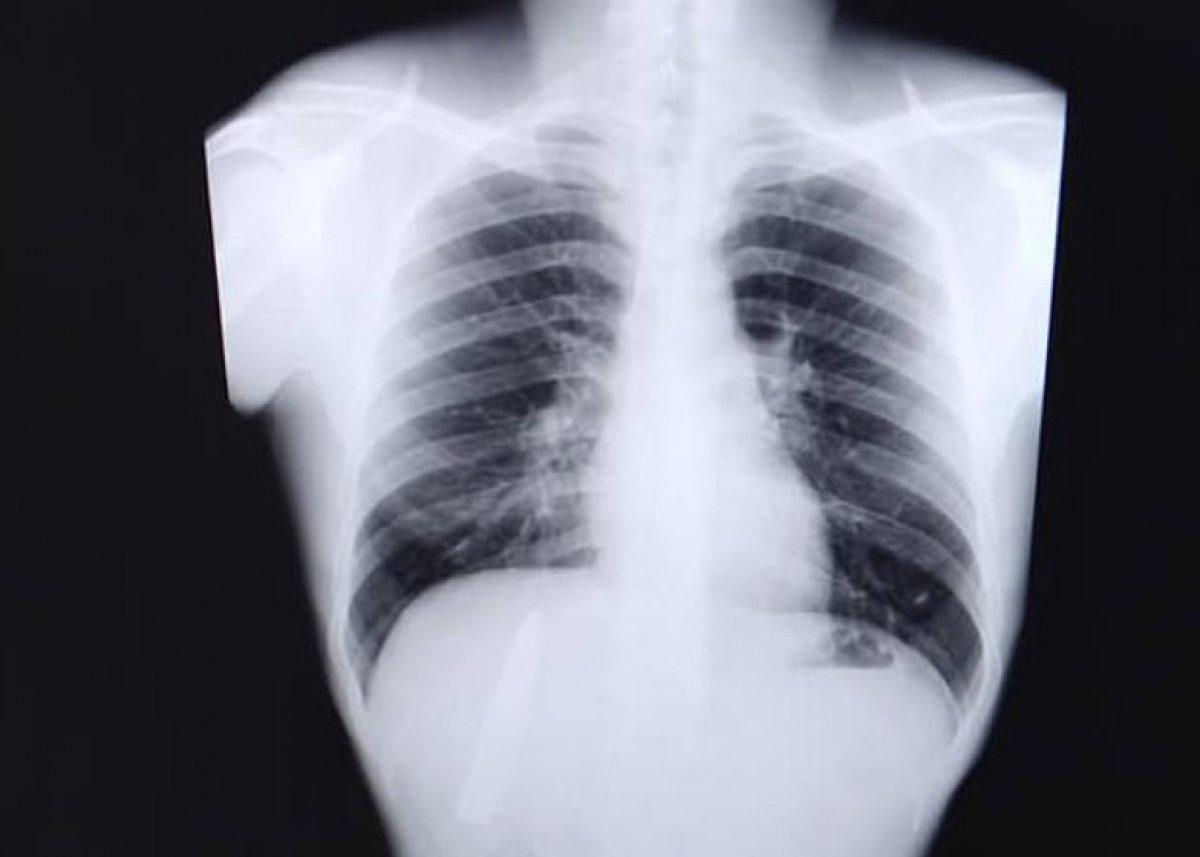

Tomao, yaşadıklarını "Hava soğukken göğsümde neden ağrı hissettiğimi hep merak ediyordum ancak içinde bıçak olduğu konusunda fikrim yoktu." ifadesiyle aktardı.

25 yaşındaki Tomao, 15 ay önce yaşadığı olayda bıçağın akciğerlerine yakın bir yerde saplandığını öğrenince şaşkına döndü.